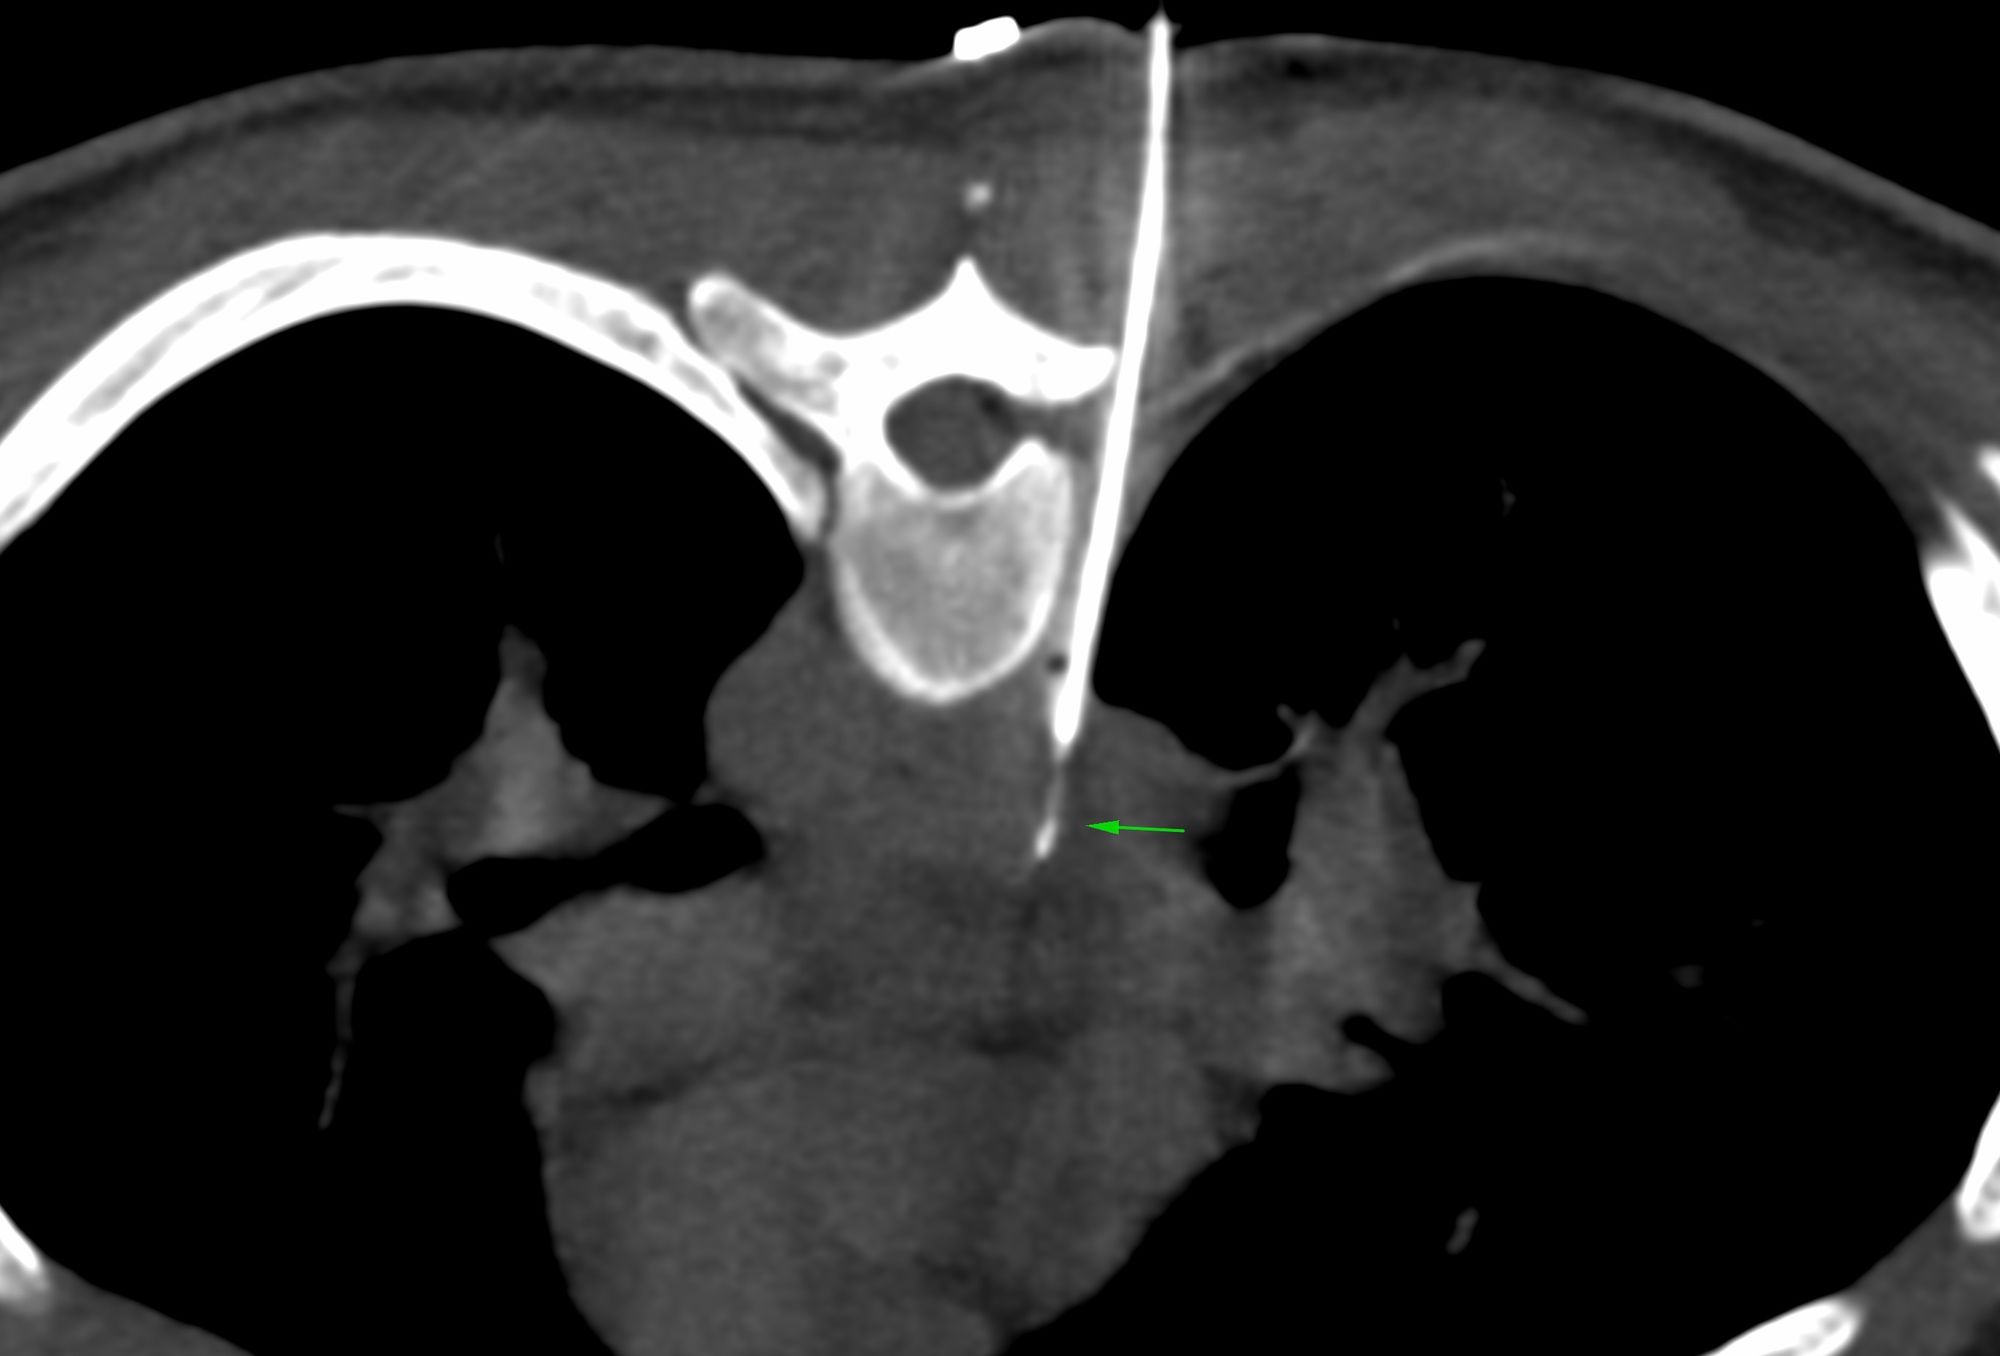

Case 30: Subcarinal Node Biopsy - Extrapleural Approach